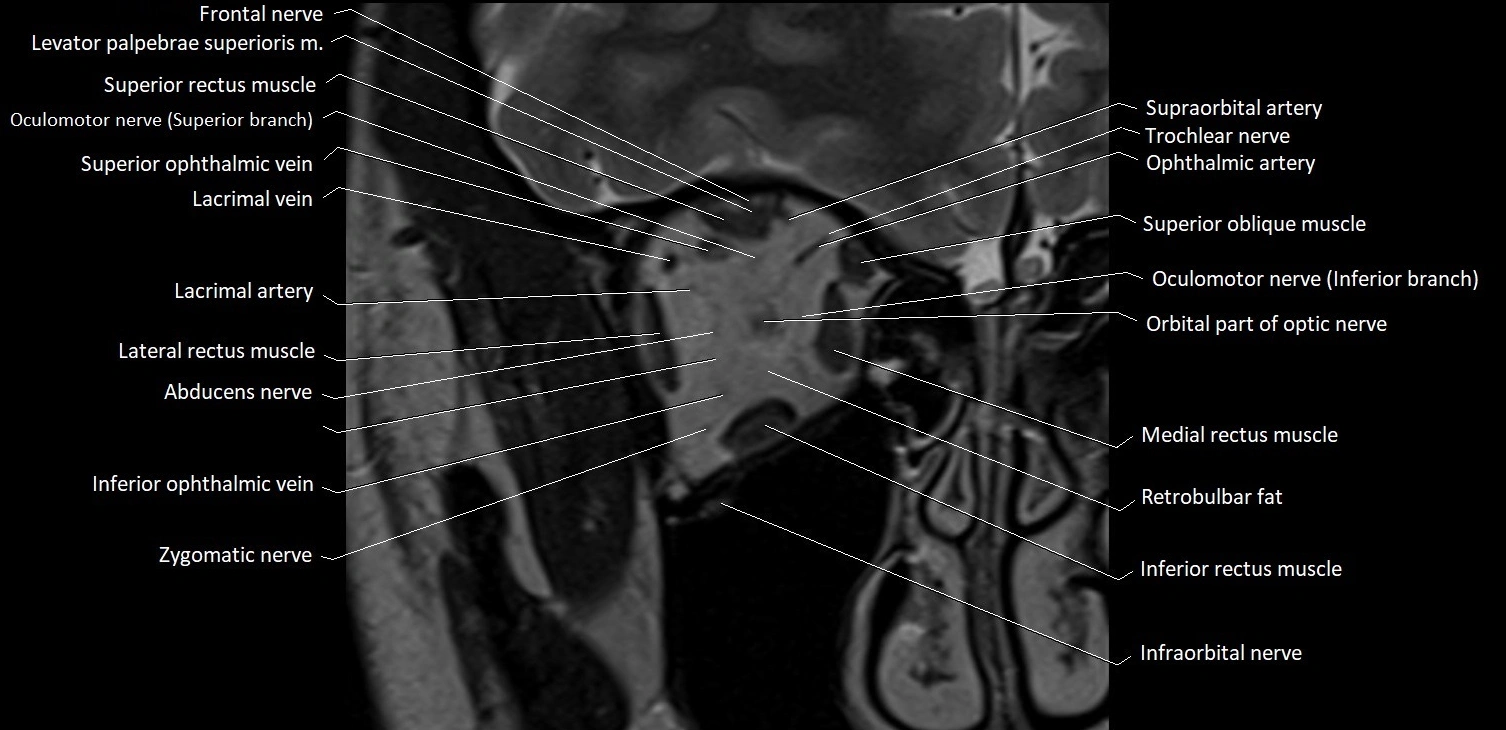

- Abducens nerve (Cranial nerve VI)

- Abducens nerve (orbital part )

- Inferior ophthalmic vein

- Infraorbital nerve

- Lacrimal artery

- Lacrimal vein

- Lateral rectus muscle

- Medial rectus muscle

- Oculomotor nerve (Superior branch)

- Oculomotor nerve (inferior branch)

- Orbital part of optic nerve

- Retrobulbar fat

- Superior oblique muscle

- Superior ophthalmic vein

- Superior rectus muscle

- Zygomatic nerve

MRI images